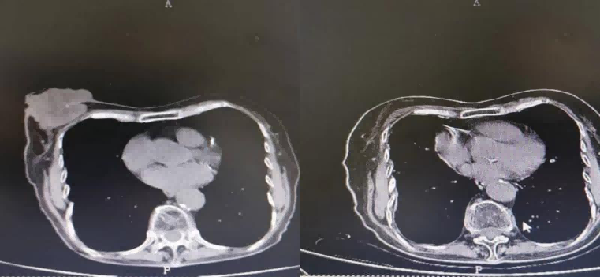

乳腺肿瘤治疗前后对比图